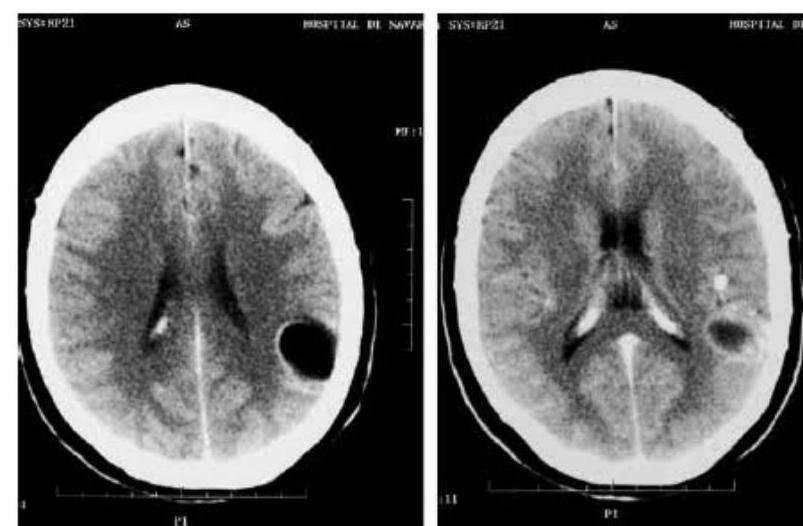

# PARASITOSIS ## DEFINICIÓN **Infecciones intestinales** generadas por **parásitos** en el ser humano, con clínicas variables y poco específicas hasta cuadros **asintomáticos**, sobre todo en adultos; prevalentes en zonas tropicales y con poca higiene debido a contaminación de alimentos o **ingesta directa**. ## EPIDEMIOLOGÍA * La frecuencia en México fluctúa del 2-39 %. * La infección por **Giardia lamblia** es el parásito entérico más frecuente a nivel mundial. * Se calcula que hay 9 millones de infectados por **Giardia lamblia** en México. * También es la más frecuente en ganado, perros y gatos. ## CUADRO COMPARATIVO | | GIARDIASIS | AMEBIASIS | TENIASIS | CISTICERCOSIS | | :--: | :--: | :--: | :--: | :--: | | AGENTE | Giardia lamblia | Entamoeba histolytica | Taenia solium (forma madura) | Quistes larvarios de Taenia solium | | CLÍNICA | Sintomática en niños<br>Diarrea aguda y crónica<br>**Síndrome de Malabsorción**<br>Pérdida de peso | Frecuentemente asintomática<br>Diarrea con moco y sangre (**Disentería**)<br>Puede haber **Abscesos Hepáticos**<br>**Amebomas** (tumores en el ciego) | Dolor abdominal y disminución del apetito.<br>Pérdida de peso.<br>Eliminación de **proglótides** por las heces. | **NEUROCISTICERCOSIS**<br>Cefalea, náusea, vómito.<br>Lesiones ocupantes (**alteraciones visuales**, **ataxia**)<br>Muerte de **quistes** en SNC: **Convulsiones** por respuesta tisular intensa | | DIAGNÓSTICO | 1. **Coproparasitoscópico** en serie de 3<br>2. **Antígeno Fecal** de Giardia en heces.<br>3. Endoscopia o **Entero-Test** | 1. **Examen directo al fresco** de heces.<br>2. **Coproparasitoscópico** | **Coproparasitoscópico** con visualización de **huevos** o **proglótides** | **RM** o **TAC** de cráneo con lesión con **realce en anillo**, **calcificaciones** o **hidrocefalia**. | | TRATAMIENTO | - **Metronidazol** | - **Metronidazol** | - **Praziquantel** | - **Albendazol** (**Neurocisticercosis**)<br>- **Praziquantel** (Cisticercosis sin neuro) | # GIARDIASIS ## DEFINICIÓN Es una enfermedad parasitaria de distribución geográfica cosmopolita, causada por el protozoo **Giardia lamblia**, que frecuentemente ocurre en niños y se caracteriza por el desarrollo de cuadros enterales agudos y crónicos, de intensidad variable y que puede ocasionar un **Síndrome de Malabsorción Intestinal**; en los adultos es comúnmente **asintomática**. ## ETIOLOGÍA Es un protozoo flagelado, mundialmente distribuido, con mecanismos de adaptación que le permiten sobrevivir a condiciones ambientales que de otro modo lo destruirían. Experimenta una variación antigénica a nivel intestinal, lo que le permite un cambio continuo de antígenos de las proteínas de superficie, inhibiendo el reconocimiento por el sistema inmune huésped. **LA FORMA INFECTANTE SON LOS QUISTES** (se adhieren al intestino delgado, produciendo más quistes que posteriormente se excretan).  ## TRANSMISIÓN: * Alimentos y aguas contaminadas (suficiente que contenga **10 quistes** de Giardia). * Animales domésticos como perro o gato. * Ganado vacuno u ovino. * Transmisión sexual oroanal. ## EPIDEMIOLOGÍA * La prevalencia mundial varía desde 1-72 %, dependiendo de la región. * El pico de enfermedad ocurre desde el inicio del verano hasta el inicio del otoño. ## FACTORES DE RIESGO * Población pediátrica (afecta mayormente a preescolares y escolares). * Estancias infantiles. * Viaje a zonas endémicas. * Mala higiene de manos. * Sexo oroanal. * Déficit selectivo de IgA. * Hipogamaglobulinemia. # CLÍNICA Curso **asintomático** desde un 9-57%. ## SÍNTOMAS DIGESTIVOS * **DOLOR ABDOMINAL** (el más común, puede presentarse solo o asociado a otros síntomas). * Considerar sospechoso si tiende a ser recurrente. * Diarrea (aguda o persistente). * Vómito. * Meteorismo. * Distensión abdominal. * Disminución del apetito. * Síndrome de Intestino Irritable. * Fatiga crónica. ## IMPACTO NUTRICIONAL * La Giardiasis afecta la nutrición de los niños debido a un **síndrome de malabsorción intestinal**. * **Retraso del crecimiento** en el 2º año de vida si se adquiere la enfermedad en etapas tempranas. * Disminución sérica de **hierro**, **zinc** y **magnesio**. * **Pobre función cognitiva**. ## OTROS HALLAZGOS Se puede observar en algunos casos lesiones en la retina en forma de degeneración "en sal y pimienta". * Artritis reactiva y sinovitis. * Dermatitis alérgica. * Prurito y urticaria. # DIAGNÓSTICO ## 1ra elección: **Coproparasitoscópicos** en serie de 3. * Se deben identificar los **trofozoítos** o **quistes** en las heces. * Es el examen rutinario de muestras de heces fecales más conocido y usado. * Se realiza en 1er y 2do nivel de atención. ## SI LOS **COPROPARASITOSCÓPICOS** RESULTAN NEGATIVOS Y **PERSISTE SOSPECHA**: ## 2da elección: **Detección de Antígeno Fecal de Giardia lamblia** en heces. Se emplean técnicas de **anticuerpos fluorescentes** y **ensayos inmunoenzimáticos**. ## ESTUDIO ENDOSCÓPICO * Visualización directa con aspirado duodenal y toma de **biopsia**. * No es un estudio de rutina y se reserva para quienes han fallado el **coproparasitoscópico** y los **antígenos fecales**. * Hallazgos en la **endoscopia**: **gastritis antral**, **duodenitis**, **úlcera duodenal**. * **Histopatológico**: infiltración de **lámina propia** por granulocitos, linfocitos y células plasmáticas, **hiperplasia linfoide nodular** y **atrofia de vellosidades intestinales**. ## ENTERO-TEST * Se requiere que el paciente trague la cápsula y la cuerda. * Posteriormente se visualiza con microscopio y tinción directa posterior a obtener la cuerda. * Requiere personal experimentado y se realiza solo en el 2do nivel. ## PCR * Es un estudio muy **sensible** y **específico** y permite identificar la **morfología** del parásito. * Pocos laboratorios cuentan con este estudio y solo se realiza con fines de investigación en el 3er nivel. # TRATAMIENTO Debido a que los pacientes **asintomáticos** con infección por Giardia lamblia expulsan los quistes y se convierten en fuente de infección para su comunidad y entorno, se debe **INICIAR TRATAMIENTO EN TODOS LOS CASOS**. ## 1ra elección: **Metronidazol** * Tiene una eficacia de 60-100% en adultos y niños. * Dosis: 5 mg/kg/dosis 3 veces al día por 5 días. * Debe suspenderse si presenta intolerancia al medicamento. * Evitar alcohol por reacción **Disulfiram**: Inhibición de la oxidación del alcohol por bloqueo de la enzima aldehído deshidrogenasa, provocando una elevación de niveles de acetaldehído. ## 2da elección: **Tinidazol en monodosis** * En caso de que el Metronidazol no sea bien tolerado. * Indicado en niños de poblaciones de bajos recursos. ## ALTERNATIVAS: * **Metronidazol** + **Albendazol** (en caso de resistencia). * **Paromomicina** (indicada en 1er trimestre de embarazo). * **Secnidazol**. * **Albendazol**. * **Furazolidona**. * **Nitazoxanida**. ## PERSISTENCIA DE LOS SÍNTOMAS * Resistencia farmacológica. * Cura seguida de **reinfección**. * Falta de apego al tratamiento. * Intolerancia a la **lactosa post-giardiasis**. * Inmunodeficiencias. ## EVALUACIÓN POSTERIOR Vigilar de manera rutinaria con nuevas muestras fecales a los 3-5 días de finalizar el tratamiento. ## REFERENCIA Envío a 2do nivel: * Síntomas sugestivos de Giardia lamblia + **Coproparasitoscópico** seriados negativos. Envío a 3er nivel: * Síntomas + **Coproparasitoscópico** Negativos + **Antígeno fecal** negativo. # AMEBIASIS ## DEFINICIÓN Es una infección intestinal parasitaria, de distribución mundial y provocada por la **Entamoeba histolytica** que tiene como hábitat el intestino grueso. Su característica es que puede presentar **diseminación hematógena**, provocando un **absceso hepático**, así como **amebomas** en el colon. ## ETIOLOGÍA La **Entamoeba** presenta dos formas: **TROFOZOÍTO**: forma vegetativa invasora, plasma hialino, puede contener glóbulos rojos. **QUISTE**: Forma resistente a los antibióticos. Esférico de 10-15 micras (**ELEMENTO INFECTANTE**). ## Transmisión: * Agua y alimentos contaminados. * Fecal/Oral. * Contacto directo. * Fómites. * Transmisores biológicos. ## EPIDEMIOLOGÍA * Es más frecuente en áreas tropicales o subtrópicas. * La presentación **EXTRAINTESTINAL** más frecuente se sitúa en el **HÍGADO** (formando **absceso hepático**). ## FACTORES DE RIESGO * Contaminación fecal de agua y alimentos. * Mala higiene de manos. # FACTORES PARA FORMACIÓN DE ABSCESO: * Sexo masculino. * 3ra a 5ta década de la vida. * Alcoholismo. * Padecimientos oncológicos. * Prácticas homosexuales. * Inmunosupresión. * Habitar o viajar a zonas endémicas. * Uso de corticosteroides. ## CLÍNICA ## ASINTOMÁTICO Es la presentación más **frecuente**. ## DIARREA * Con **disentería grave** (moco y sangre). * Puede haber **ulceración colónica**. ## ABSCESO HEPÁTICO * Fiebre vespertina o nocturna no muy alta. * Dolor en hipocondrio derecho. * Hepatomegalia. * Ictericia. * Escalofríos y malestar general. ## AMEBOMAS * Masas pseudotumorales en el ciego. ## DIAGNÓSTICO 1. **EXAMEN DIRECTO AL FRESCO DE HECES** (serie de 3) o secreciones. a. Búsqueda de **trofozoítos**. b. Es el estudio diagnóstico definitivo. 2. **COPROPARASITOLÓGICO** de concentración, para amebiasis crónica. a. Búsqueda de **quistes** (3 series). 3. **BIOPSIAS DE ÚLCERAS** (**trofozoítos**). a. Se realiza con tinción de **hematoxilina**. # TRATAMIENTO ## 1ra elección: **Metronidazol**, **Tinidazol** o **Cloroquina** * Son **amebicidas tisulares**. ## 2da elección: **Paromomicina**, **Ioquinol**, **Furoato de Diloxanida** * Son **amebicidas luminales**. ## PORTADORES ASINTOMÁTICOS En caso de detectarse familiares de infectados pero **asintomáticos**, se iniciará un **fármaco luminal**. 1ra elección: **Yodoquinol** por 20 días. ## ABSCESO HEPÁTICO AMEBIANO 1ra elección: **Metronidazol** + **amebicida intraluminal** (**Furoato de Diloxanida**, **Paromomicina**). ## 2da elección: * Si hay intolerancia a **Metronidazol** o **Tinidazol**. * Si hay intolerancia a **imidazoles** o **Nitazoxanida**. ## PUNCIÓN PERCUTÁNEA * Persistencia de síntomas clínicos de 72 horas de iniciado el tratamiento. * Datos de ruptura inminente. * Absceso de lóbulo hepático izquierdo. * Embarazo y contraindicación del uso de Metronidazol. * Complicaciones pleuropulmonares. ## ABORDAJE LAPAROSCÓPICO * Drenaje por esta vía si hay fracaso en el percutáneo. ## ABORDAJE LAPAROTOMÍA * En caso de ruptura del absceso a cavidad peritoneal. ## FACTORES DE MAL PRONÓSTICO ABSCESO HEPÁTICO * Abscesos múltiples. * Volumen >500 ml. * Elevación del hemidiafragma derecho (o derrame pleural). * Bilirrubina >3.5 mg/dL. * Hemoglobina <8 mg/dL. * Albúmina <2 g/dL. * Diabetes mellitus. # TENIASIS ## DEFINICIÓN La infección por **Taenia solium** es una infección intestinal por **TENIAS ADULTAS**, que se produce tras la **ingestión** de **carne de cerdo contaminada** o de carne ovina en el caso de **Taenia saginata**, madurando en el intestino. ## ETIOLOGÍA El ser humano es el **huésped definitivo**. * Taenia solium. * Taenia saginata. 1. Los seres humanos ingieren **carne de cerdo con cisticercos** (**larvas**) cruda o poco cocinada. 2. Después de la ingestión, los **quistes** se evaginan, se adhieren al intestino delgado por sus **escólices** y maduran para convertirse en **tenias adultas** en unos 2 meses. 3. Las **tenias adultas** producen **proglótides**. Las **proglótides grávidas** se desprenden de la tenia y migran hacia el ano. 4. Tras desprenderse, las **proglótides** o los **huevos** salen del **huésped definitivo** (humano) a través de las heces. 5. Los cerdos o los seres humanos se infectan al ingerir **huevos embrionados** o **proglótides grávidas** (p. ej., en alimentos contaminados con materia fecal). La **autoinfección** puede producirse en los seres humanos si las `proglótides` pasan del intestino al estómago por movimientos antiperistálticos.  6. Una vez ingeridos los **huevos**, se incuban en el intestino y liberan **oncosferas**, que penetran en la **pared intestinal**. 7. Las **oncosferas** se desplazan por el **torrente sanguíneo** hasta los **músculos estriados**, el **encéfalo**, el **hígado** y otros órganos, donde se convierten en **cisticercos**. En estos pacientes, puede producirse la **cisticercosis**. **PROGLÓTIDE**: es lo que se encuentra en las heces y por lo general es el motivo de consulta al observarlo en las evacuaciones. La **taenia** suele alcanzar los 4 metros de longitud (se suman los `proglótides` y el `escólex`). # EPIDEMIOLOGÍA Las **tenias adultas** pueden residir en el intestino delgado durante varios años; pueden alcanzar los 2 a 7 m de longitud y producir hasta 1.000 **proglótides**, cada una con alrededor de **50.000 huevos**. El ser humano es el **huésped definitivo**.  ## FACTORES DE RIESGO * Carne mal cocida. * Viaje a zonas endémicas. * Contaminación fecal de agua y alimentos. ## CLÍNICA * Excreción **asintomática** de **proglótides**. * **Náusea**, **anorexia**, **dolor epigástrico**. ## DIAGNÓSTICO  ## **Coproparasitoscópico** **Visualización** de **huevos** o **proglótides**. * La infección por **gusanos adultos** de *T. solium* suele poder diagnosticarse mediante el **examen microscópico** de muestras de heces y la identificación de **huevos**, **proglótides** o ambos. * Los huevos de *T. solium* se encuentran en \leq 50% de las muestras de heces de pacientes con **cisticercosis**. * Los huevos son indistinguibles de los de *T. saginata* y *T. asiatica*. ## TRATAMIENTO ## 1ra elección: **Praziquantel** * Una sola dosis de 5 a 10 mg/kg de **prazicuantel** por vía oral para eliminar los **helmintos adultos**. * Provoca alteración en el flujo de iones de calcio de las células del parásito, generando una contracción muscular y paralizándolo. * Precaución en pacientes que también tienen **neurocisticercosis**, porque al matar los **quistes**, el **prazicuantel** puede desencadenar una **respuesta inflamatoria** asociada con **convulsiones** u otros síntomas. # CISTICERCOSIS ## DEFINICIÓN La **cisticercosis** es una infección parasitaria de los tejidos causada por los **QUISTES larvarios** de la tenia porcina. Estos **quistes** infectan el **cerebro**, los músculos y otros tejidos y son una de las causas principales de **epilepsia** en los adultos de la mayoría de los países de bajos ingresos. Una persona puede contraer cisticercosis al **ingerir los huevos** excretados por alguien que tiene **tenia intestinal**. ## ETIOLOGÍA Los **cisticercos** son una forma intermedia en el desarrollo del parásito (entre el embrión y el hexacanto). Los que producen **neurocisticercosis** son las especies de *Taenia solium*. En la mayoría de los órganos, los **cisticercos viables** (**larvas**) causan una **reacción tisular mínima** o nula, pero la muerte de los **quistes** en el **SNC** puede desencadenar una **respuesta tisular intensa**. En consecuencia, los síntomas suelen no evidenciarse hasta varios años después del contagio. ## EPIDEMIOLOGÍA * La **cisticercosis** no se contrae por comer carne de cerdo mal cocida (**Teniasis**) sino por la **ingesta** de **larvas** (**huevos** o formas inmaduras de la **Taenia**) excretadas en las heces humanas. * Las personas que viven en el mismo hogar del portador de la tenia tienen un riesgo más alto de contraer cisticercosis que otras personas. ## FACTORES DE RIESGO * Zonas de América Latina, Asia y África donde haya malas condiciones de saneamiento. * Cría de cerdos sueltos que pueden estar en contacto con heces humanas. ## CLÍNICA El **cisticerco** puede afectar al músculo y al **sistema nervioso central**. ## NEUROCISTICERCOSIS * **Lesiones quísticas** que evolucionan a **calcificaciones**. * **Cefalea**. * **Náusea** y **vómito**. * **Alteraciones visuales**. * Inestabilidad. * **Ataxia**. ## **Convulsiones**: Relacionadas con la **inflamación** que rodea los **cisticercos** en el **parénquima cerebral**, **hidrocefalia** por obstrucción del drenaje del **LCR**. # DIAGNÓSTICO ## **TAC** / **RM** * Revela **nódulos sólidos**, **cisticercos**, **quistes calcificados**. * Lesiones con **REALCE DE CONTRASTE EN ANILLO**. * **Hidrocefalia**.  ## ELISA * Puede realizarse en **LCR** o sangre. * Revela **anticuerpos anti-cisticerco**.  **Figura 1**. TAC craneal donde se observa una lesión **quística** de 3 cm de diámetro, con **calcificaciones nodulares** en su periferia, que se corresponde con una **neurocisticercosis**. Quística Coloidal Calcificada  ## TRATAMIENTO ## NEUROCISTICERCOSIS ## 1ra elección: **Albendazol** durante 7-14 días. * Si hay **quistes cerebrales** y se utiliza **Praziquantel**, puede desatar una **respuesta inflamatoria** asociada a **convulsiones**. * El mecanismo de acción es a través de la **INHIBICIÓN DE LA ENZIMA FUMARATO REDUCTASA**, daña de forma selectiva los **microtúbulos citoplasmáticos** de las células intestinales de los nemátodos pero no del huésped, ocasionando ruptura de las células y pérdida de la **funcionalidad secretora y absortiva**. * Los **cisticercos calcificados** no se tratan. ## **Esteroides** * Indicados cuando existe gran cantidad de **cisticercos** en el cerebro para reducir la **respuesta inflamatoria** durante su destrucción, para evitar **crisis convulsivas**. * La suspensión repentina del esteroide puede provocar **edema perilesional**, debe suspenderse paulatinamente en el lapso de 2 semanas. ## CISTICERCOSIS ## 1ra elección: **Praziquantel**

# PARASITOSIS ## DEFINICIÓN Infecciones intestinales generadas por parásitos en el ser humano con clínicas variables y poco específicas hasta cuadros asintomáticos, sobre todo en adultos; prevalentes en zonas tropicales y con poca higiene debido a contaminación de alimentos o infesta directa. ## EPIDEMIOLOGÍA - La frecuencia en México fluctúa del 2 - 39 % - La infección por GIARDIA LAMBLIA es el parásito entérico más frecuente a nivel mundial. - Se calcula que hay 9 millones de infectados por Giardia Lamblia en México - También es la más frecuente en ganado, perros y gatos. ## CUADRO COMPARATIVO | | GIARDIASIS | AMEBIASIS | TENIASIS | CISTICERCOSIS | | :--: | :--: | :--: | :--: | :--: | | AGENTE | Giardia lamblia | Entamoeba histolytica | Taenia Solium (forma madura) | Quistes larvarios de Taenia Solium | | CLÍNICA | Sintomática en niños Diarrea aguda y crónica Síndrome de Malabsorción Pérdida de peso | Frecuentemente asintomática Diarrea con moco y sangre (Disentería) Puede haber Abscesos Hepáticos Amebomas (tumores en el ciego) | Dolor abdominal y disminución apetito. Pérdida de peso. Eliminación de proglótides por las heces. | NEUROCISTICERCOS Cefalea, náusea, vómito. Lesiones ocupantes (alteraciones visuales, ataxia) Muerte de quistes en SNC: Convulsiones por respuesta tisular intensa | | DIAGNÓSTICO | 1. Coproparasitoscópico en serie de 3 2. Antígeno Fecal de Giardia en heces. 3. Endoscopia o EnteroTEST | 1. Examen directo al fresco de heces. 2. Coproparasitoscópico | Coproparasitoscópico con visualización de huevos o proglótides | RMN o TAC de cráneo con lesión con realce en anillo, calcificaciones o hidrocefalia. | | TRATAMIENTO | - Metronidazol | - Metronidazol | - Praziquantel | - Albendazol (Neuro) - Praziquantel (Cisticercosis sin neuro) | # CIARDASIS ## DEFINCIÓN Es una enfermedad parasitaria de distribución geográfica cosmopolita causa por el protozoo Giardia lamblia, frecuentemente ocurre en los niños y se caracteriza por el desarrollo de cuadros enterales agudos y crónicos, de intensidad variable y que puede ocasionar un Síndrome de Malabsorción Intestinal; en los adultos es comúnmente asintomática. ## ETIOLOGÍA Es un protozoo flagelado, mundialmente distribuido, con mecanismos de adaptación que le permiten sobrevivir a condiciones ambientales que de otro modo lo destruirían. Experimenta una variación antigénica a nivel intestinal, lo que le permite un cambio continuo de antígenos de las proteínas de superficie, inhibiendo el reconocimiento por el sistema inmune huésped. LA FORMA INFECTANTE SON LOS QUISTES (se adhieren al intestino delgado, produciendo más quistes que posteriormente se excretan).  ## TRANSMISIÓN: - Alimentos y aguas contaminadas (suficiente que tenga 10 quistes de Giardia) - Animales domésticos como perro o gato - Ganado vacuno u ovino - Transmisión sexual oral-anal. ## EPIDEMIOLOGÍA - La prevalencia mundial va desde 1-72 % dependiendo de la región. - El pico de enfermedad ocurre a inicio de verano hasta el inicio del otoño. ## FACTORES DE RIESGO - Población pediátrica (afecta mayormente a preescolares y escolares) - Estancias infantiles - Viaje a zonas endémicas - Mala higiene de manos - Sexo oral anal - Déficit selectivo de IgA - Hipogamaglobulinemia # CLINICA Curso asintomático desde un 9 - 57%. ## SÍNTOMAS DIGESTIVOS - DOLOR ABDOMINAL (el más común, puede presentarse solo o asociado a otros síntomas) - Considerar sospechoso si tiende a ser recurrente. - Diarrea (aguda o persistente) - Vómito - Meteorismo - Distensión abdominal - Disminución del apetito - Síndrome de Intestino Irritable - Fatiga crónica ## IMPACTO ESTADO NUTRICIONAL - La Giardiasis afecta la nutrición de los niños debido a un síndrome de malabsorción intestinal. - Retraso del crecimiento en el 2º año de vida si se adquiere la enfermedad en etapas tempranas de vida. - Disminución sérica de Hierro, Zinc y Magnesio. - Pobre función cognitiva. ## OTROS HALLAZGOS Se puede observar en algunos casos lesiones en la retina en forma de degeneración "en sal y pimienta". - Artritis reactiva y sinovitis - Dermatitis alérgica - Prurito y urticaria # DIAGNÓSTICO ## 1ra elección: COPROPARASITOSCÓPICOS EN SERIE DE 3. - Se deben identificar los Trofozoítos o quistes en las heces. - Es el examen rutinario de muestras de heces fecales más conocido y usado. - Se realiza en 1^{\text {o }} y 2^{\circ} nivel de atención ## SI LOS COPROPARASITOSCÓPICOS RESULTAN NEGATIVOS Y PERSITE SOSPECHA: ## 2da elección: DETECCIÓN DE ANTÍGENO FECAL DE GIARDIA LAMBLIA EN HECES Se emplean técnicas de anticuerpos fluorescentes y ensayos inmunoenzimáticos ## ESTUDIO ENDOSCÓPICO - Visualización directa con aspirado duodenal y toma de biopsia - No es un estudio de rutina y se reserva para quienes ha fallado el Coproparasitoscópico y los Antígenos fecales. - Hallazgos Endoscopia: gastritis antral, duodenitis, úlcera duodenal. - Histopatológico: infiltración de lámina propia por granulocitos, linfocitos y células plasmáticas, hiperplasia linfoide nodular y atrofia de vellosidades intestinales. ## ENTERO-TEST - Se requiere que el paciente trague la cápsula y la cuerda. - Posteriormente se visualiza con microscopio y tinción directa posterior a obtener la cuerda. - Requiere personal experimentado y solo en 2 o nivel. ## PCR - Es un estudio muy sensible y específico y permite identificar la morfología del parásito. - Pocos laboratorios cuentan con este estudio y solo se realiza con fines de investigación en 3o nivel. # TRATAMIENTO Debido a que los pacientes asintomáticos con infección con Giardia lamblia expulsan los quistes y se convierten en fuente de infección para su comunidad y entorno, se debe INICIAR TRATAMIENTO EN TODOS LOS CASOS. ## 1ra elección: METRONIDAZOL - Tiene una eficacia de 60-100 % en adultos y niños. - Dosis 5 mg / kg / dosis 3 veces al día por 5 días. - Debe suspenderse si presenta intolerancia al medicamento. - Evitar alcohol por reacción Disulfiram - Inhibición de la oxidación del alcohol por bloqueo de la enzima aldehído deshidrogenasa, provocando una elevación de niveles de acetaldehído ## 2da elección: TINIDAZOL EN MONODOSIS - En caso de que el Metronidazol no sea bien tolerado. - Indicado en niños de poblaciones de bajos recursos. ## ALTERNATIVAS: - Metronidazol + Albendazol (en caso de resistencia). - Paromomicina (indicada en 1o trimestre de embarazo). - Secnidazol - AlbendazolFurazolidona - Nitazoxanida ## PERSISTENCIA DE LOS SÍNTOMAS - Resistencia farmacológica - Cura seguida de re infección - Fatla de apego al tratamiento - Inotlerancia a lactosa post-giardiasis - Inmunodeficiencias. ## EVALUACIÓN POSTERIOR Vigilar de manera rutinaria con nuevas muestras fecales a los 3-5 días de finalizar el tratamiento. ## REFERENCIA Envío a 20 nivel: - Síntomas sugestivos de Giardia Lamblia + Coproparasitoscópico seriados negativos. Envío a 30 nivel: - Síntomas + Coproparasitoscópico Negativos + Antígeno fecal negativo. # AIIEBIRSIS ## DEFINICIÓN Es una infección intestinal parasitaria, de distribución mundial y provocada por la Entamoeba histolytica que tiene como hábitat el intestino grueso. Su característica es que puede presentar diseminación hematógena, provocando un absceso hepático, así como Amebomas en el colon. ## ETIOLOGÍA La Entamoeba presenta dos formas: TROFOZOÍTO: forma vegetativa invasora, plasma hialino, puede contener glóbulos rojos. QUISTE: Forma resistente a los antibióticos. Esférico de 10-15 micras (ELEMENTO INFECTANTE) ## Transmisión: - Agua y alimentos contaminados. - Fecal/Oral - Contacto directo - Fomites - Transmisores biológicos ## EPIDEMIOLOGÍA - Es más frecuente en áreas tropicales o subtrópicas. - La presentación EXTRAINTESTINAL más frecuente se sitúa en el HÍGADO (fromando absceso hepático) ## FACTORES DE RIESGO - Contaminación fecal de agua y alimentos - Mala higiene de manos # FACTORES PARA FORMACIÓN DE ABSCESO: - Sexo masculino - 3 \circ a 5^{\circ} década de la vida - Alcoholismo - Padecimientos oncológicos - Prácticas homosexuales - Inmunosupresión - Habitar o viajar a zonas endémicas - Uso de corticosteroides ## CLÍNICA ## ASINTOMÁTICO - Es la presentación más frecuente ## DIARREA - Con disentería grave (moco y sangre) - Puede haber ulceración colónica ## ABSCESO HEPÁTICO - Fiebre vespertina o nocturna no muy alta. - Dolor en hipocondrio derecho - Hepatomegalia - Icterica - Escalofríos y malestar general. ## AMEBOMAS - Masas pseudotumorales en el ciego en CSD. ## DIAGNOSTICO 1. EXAMEN DIRECTO AL FRESCO DE HECES (SERIE DE 3) O SECRECIONES. a. Búsqueda de presencia de trofozoítos b. Es el estudio diagnóstico definitivo. 2. COPROPARSITOLÓGICO DE CONCENTRACIÓN, PARA AMIBIASIS CRÓNICA. a. búsqueda de quistes (3 series) 3. BIOPSIAS DE ÚLCERAS (TROFOZOÍTOS) a. Se realiza con Tinción de Hematosoina # TRATAMIENTO ## 1ra elección: METRONIDAZOL, TINIDAZOL O CLOROQUINA - Son amebicidas tisulares ## 2da elección: PAROMICINA, IOQUINOL, FUROATO DE DILOXANIDA - Son amebicidas luminales. ## PORTADORES ASINTOMÁTICOS En caso de detectarse familiares de infectado pero asintomáticos se iniciará un fármaco luminal. 1ra elección: YODOQUINOL por 20 días. ## ABSCESO HEPÁTICO AMEBIANO 1ra elección: METRODINAZOL + AMICIDA INTRALUMINAL (Furoato de Diloxanida, Paromicina). ## 2da elección: - Si hay intolerancia a Metroniazol - Tinidazol - Si hay intolerancia a Imidazoles - Nitazoxanida ## PUNCIÓN PERCUTÁNEA - Persistencia de síntomas clínicos de 72 horas de iniciado el tratamiento. - Datos de ruptura inminente - Absceso de lóbulo hepático izquierdo - Embarazo y contraindicación del uso de Metronidazol - Complicaciones pleuropulmonares. ## ABORDAJE LAPAROSCÓPICO - Drenaje por esta vía si hay fracaso en el percutáneo. ## ABORDAJE LAPAROTOMÍA - En caso de ruptura del absceso a cavidad peritoneal. ## FACTORES DE MAL PRONÓSTICO ABSCESO HEPÁTICO - Abscesos múltiples - Volumen >500 ml - Elevación del hemidiafragma derecho ( o derrame pleural) - Bilirrubina >3.5 mg / dL - Hemoglobina <8 mg / dL - Albúmina <2 ~g / dL - Diabetes mellitus. # TEPIASIS ## DEFINICIÓN La infección por Taenia solium es una infección intestinal por TENIAS ADULTAS, que se produce tras la ingestión de carne de cerdo contaminada o de carne ovina en el caso de Taenia saginata, madurando en el intestino. ## ETIOLOGÍA El ser humano es un huésped intermediario. - Taenia solium - Taenia saginata 1. Los seres humanos ingieren carne de cerdo con cisticercos (larvas) cruda o poco cocinada. 2. Después de la ingestión, los quistes se evaginan, se adhieren al intestino delgado por sus escólices y maduran para convertirse en tenias adultas en unos 2 meses. 3. Las tenias adultas producen proglótides. Las proglótides grávidas se desprenden de la tenia y migran hacia el ano. 4. Tras desprenderse, las proglótides o los huevos salen del huésped definitivo (humano) a través de las heces. 5. Los cerdos o los seres humanos se infectan al ingerir huevos embrionados o proglótides grávidas (p. ej., en alimentos contaminados con materia fecal). La autoinfección puede producirse en los seres humanos si las proglótides pasan del intestino al estómago por movimientos antiperistálticos.  6. Una vez ingeridos los huevos, se incuban en el intestino y liberan oncosferas, que penetran en la pared intestinal. 7. Las oncosferas se desplazan por el torrente sanguíneo hasta los músculos estriados, el encéfalo, el hígado y otros órganos, donde se convierten en cisticercos. En estos pacientes, puede producirse la cisticercosis. PROGLÓTIDE: es lo que se encuentra en las heces y por lo general es el motivo de consulta al observarlo en las evacuaciones, La taeina suelen alcanzar los 4 metros de longitud (se suman los proglótides y el escólex). # EPIDEMIOLOGÍA Las tenias adultas pueden residir en el intestino delgado durante varios años; pueden alcanzar los 2 a 7 m de longitud y producir hasta 1.000 proglótides, cada una con alrededor de \mathbf{5 0 . 0 0 0} huevos. El ser humano es el huésped definitivo.  ## FACTORES DE RIESGO - Carne mal cocida - Viaje a zonas endémicas - Contaminación fecal de agua y alimentos ## CLÍNICA - Excreción asintomática de proglótides - Nausea anorexia, dolor epigástrico. ## DIAGNÓSTICO  ## COPROPARASITOSCÓPICO Visualización de huevos o proglótides. - La infección por gusanos adultos de T. solium suele poder diagnosticarse mediante el examen microscópico de muestras de heces y la identificación de huevos, proglótides o ambos. - Los huevos de T. solium se encuentran en \leq 50 % de las muestras de heces de pacientes con cisticercosis. - Los huevos son indistinguibles de los de T. saginata y T. asiatica. ## TRATAMIENTO ## 1ra elección: PRAZIQUANTEL - Una sola dosis de 5 a 10 mg / kg de prazicuantel por vía oral para eliminar los helmintos adultos. - Provoca alteración en el flujo de iones de calcio de las células del parásito, generando una contracción muscular y paralizándolo. - Precaución en pacientes que también tienen neurocisticercosis, porque al matar los quistes, el pracicuantel puede desencadenar una respuesta inflamatoria asociada con convulsiones u otros síntoma. # CISTICERCOSIS ## DEFINICIÓN La cisticercosis es una infección parasitaria de los tejidos causada por los QUISTES larvarios de la tenia porcina. Estos quistes infectan el cerebro, los músculos y otros tejidos y son una de las causas principales de epilepsia en los adultos de la mayoría de los países de bajos ingresos. Una persona puede contraer cisticercosis al ingerir los huevos excretados por alguien que tiene tenia intestinal. ## ETIOLOGÍA Los cisticercos son una forma intermedia en el desarrollo del parásito (entre el embrión y el hexacanto). Los que producen Neurocisticercos son las especies de Taenia solium. En la mayoría de los órganos, los cisticercos viables (larvas) causan una reacción tisular mínima o nula, pero la muerte de los quistes en el SNC puede desencadenar una respuesta tisular intensa. En consecuencia, los síntomas suelen no evidenciarse hasta varios años después del contagio. ## EPIDEMIOLOGÍA - La cisticercosis no se contrae por comer carne de cerdo mal cocida (esa es la Teniasis) sino por la ingesta de larvas (huevos o formas inmaduras de la Taenia) excretadas en las heces humanas. - Las personas que viven en el mismo hogar del portador de la tenia tienen un riesgo más alto de contraer cisticercosis que otras personas. ## FACTORES DE RIESGO - Zonas de América Latina, Asia y África donde haya malas condiciones de saneamiento. - Cría de cerdos sueltos que pueden estar en contacto con heces humanas. ## CLINICA El cisticercos puede afectar al músculo y al sistema nervioso central. ## NEUROCISTICERCOS - Lesiones quísticas que evolucionan a calcificaciones - Cefalea - Náusea y vómito - Alteraciones de la vista - Inestabilidad - Ataxia ## CONVULSIONES: Relacionadas a la inflamación que rodea los cisticercos en el parénquima cerebral, hidrocefalia por obstrucción de drenaje del LCR. # DIANGÔSTICO ## TAC / RMN - Revela nódulos sólidos, cisticercos, quistes calcificados. - Lesiones con REALCE DE CONTRASTE EN ANILLO - Hidrocefalia  ELISA - Puede realizarse en LCR o Sangre - Revela anticuerpos anti-Cisticercos.  Figura 1. TAC craneal donde se observa una lesión quística de 3 cm de diámetro, con calcificaciones nodulares en su periferia, que se corresponde con una mercisiticercosis. Quística Coloidal Calcificada  ## TRATAMIENTO ## NEUROCISTICERCOSIS ## 1ra elección: ALBENDAZOL durante 7 - 14 días. - Si hay quistes cerebrales y se utiliza Praziquantel, puede desatar una respuesta inflamatoria asociada a convulsiones. - El mecanismo de acción es a través de la INHIBICIÓN DE LA ENZIMA FUMARATO REDUCTASA, daña de forma selectiva los microtúbulos citoplasmáticos de las células intestinales de los nemátodos pero no del huésped, ocasionando ruptura de las células y pérdida de la funcionalidad secretora y absortiva. - Los cisticercos calcificados no se tratan. ## ESTEROIDES - Indicados cuando existe gran cantidad de cisticercos en el cerebro para reducir respuesta inflamatoria durante su destrucción para evitar crisis convulsivas. ⌀ La suspensión repentina del esteroide puede provocar edema perilesional, debe suspenderse paulatinamente en el lapso de 2 semanas. ## CISTICERCOSIS ## 1ra elección: PRAZIQUANTEL